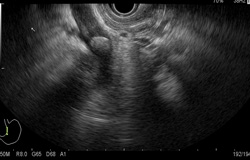

Endoscopic ultrasound (EUS) is an endoscopic procedure for imaging of the upper gastrointestinal tract (oesophagus, stomach, and duodenum), and the pancreas to biliary system (bile ducts, gallbladder, and pancreas) using a flexible endoscope equipped with a small specialized ultrasound probe.

Before undergoing EUS, patients are given sedation. A thin tube is inserted through the patient’s mouth and led down into the stomach. Once in the stomach, a small ultrasound probe at the tip of the tube emits soundwaves which produces a clear image of the desired area (such as the pancreas, digestive tract, or stomach). If masses or other signs of disease are found, a small biopsy will be taken for testing (with by EUS guided Fine Needle Aspiration (FNA).